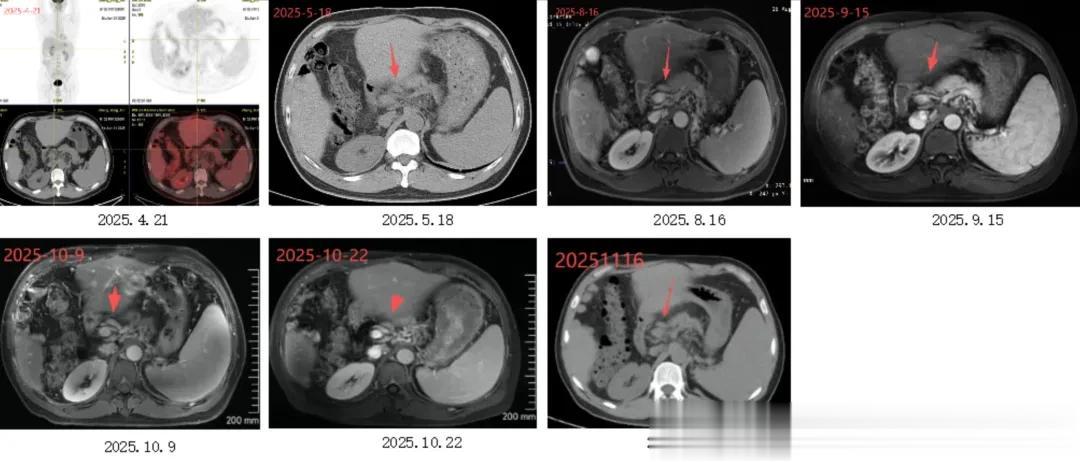

▶ 肝脏及肝周病变:尾状叶及下腔静脉区域2025年11月PET-CT显示该区域病灶消失,邻近下腔静脉淋巴结未明确显示,提示治疗有效或病灶活性抑制;

影像表现:2025.4.21PET-CT示:肝门区淋巴结肿大;2025.5、2025.8复查同前;2025.9至2025.11复查示:肝门区淋巴结略缩小。

直到2025年4月,PET-CT确认:

① 术区周围多发点状代谢增高灶,大小约13mm×9.3mm;术区边缘见多个实性结节影,大小约12mm× 9mm;

② 左肺上叶结节,大小约12mm×10mm,考虑肿瘤转移可能;

③ 右侧膈上、肝门区、腹膜后区多发淋巴结,较大者位于右侧膈上,大小约30mm×6mm,其中右侧膈上淋巴结考虑肿瘤转移可能,余淋巴结肿瘤转移不能除外。